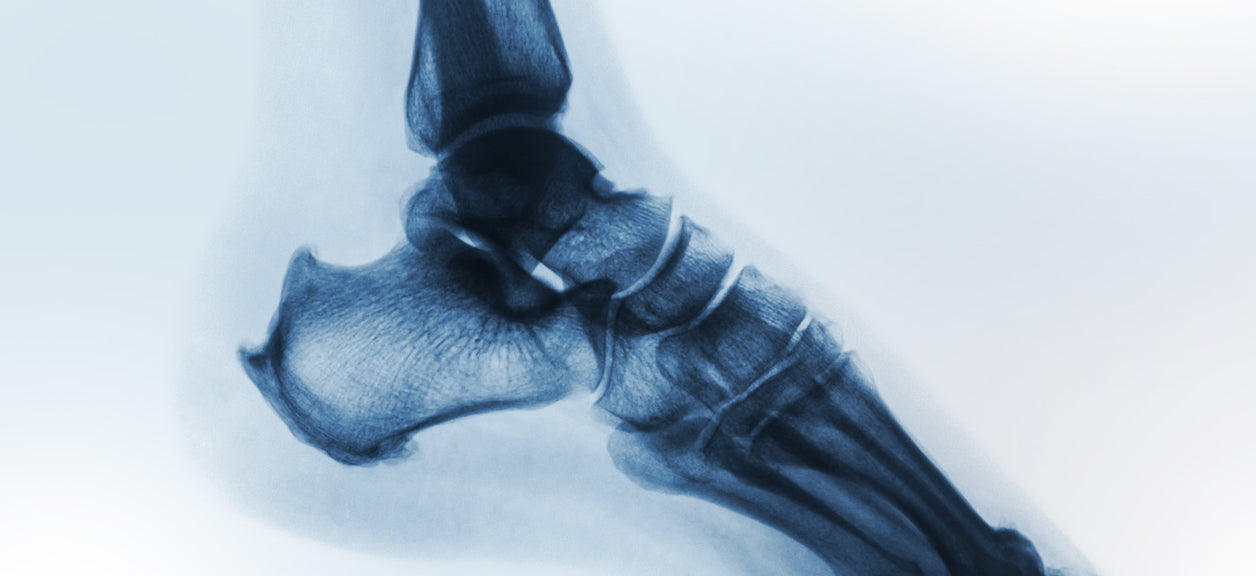

Poor air quality has a wide variety of unpleasant health consequences, such as asthma, a decrease in male fertility, and cardiovascular disease. But recent research has also shined a spotlight on another problem: an increase in the risk of developing osteoporosis.

A team of researchers from Columbia University’s Mailman School of Public Health, Northwestern University, and other institutions conducted two studies looking at the relationship between components of air pollution, like elevated levels of particulate matter and osteoporosis, a condition that results in brittle and weak bones and a greater risk of fractures.

The findings: Even a small increase in small particulate matter concentrations is associated with a rise in bone fractures among older adults. The research also documented that there is an especially high rate of admissions for bone fracture in low-income communities.

The study, which evaluated 692 middle-aged low-income men, found that individuals living in areas with higher small particulate matter and concentrations of black carbon, a component of air pollution from automotive emissions, had lower levels of a hormone that regulates calcium levels and the rebuilding of bones. As the study indicates, particulate matter is known to cause systemic oxidative damage and inflammation. Researchers suggest this characteristic of particulate matter, in particular, could accelerate bone loss and increase the risk of bone fractures.

Osteoporosis is the most common reason for fractures among the elderly. There are approximately two million osteoporosis-related bone fractures a year in the U.S., resulting in $20 billion in annual direct health costs. The consequences are serious: In addition to potentially ending the ability of an individual to live independently, the risk for death increases by as much as 20 percent.